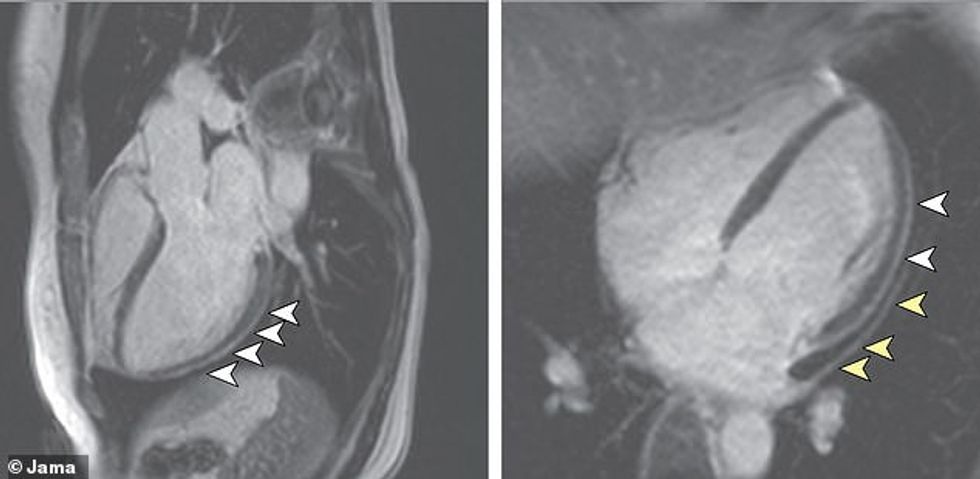

Të udhëhequr nga studiues në spitalin universitar Frankfurt në Gjermani, studimi i parë shqyrtoi masat e shëndetit kardiak në 100 njerëz që kishin mbijetuar nga infeksioni coronavirus.

Studiuesit mund të shohin shenja të dëmtimit të zemrës në MRI të marra prej 78 nga 100 të mbijetuarit.

Pothuajse 76 për qind - kishin nivele të larta të një proteine të quajtur troponin, e krahasueshme me atë që shihet tek një person që ka pësuar sulm në zemër.

60 nga pjesëmarrësit kishin shenja të inflamacionit të zemrës edhe pse mesatarisht kishin kaluar 71 ditë, pasi ishin diagnostifikuar me coronavirus. Në studimin e dytë, studiuesit nga universiteti i zemrës, në Hamburg, Gjermani, analizuan indet e zemrës nga 39 njerëz që vdiqën pas infektimit me coronavirus.